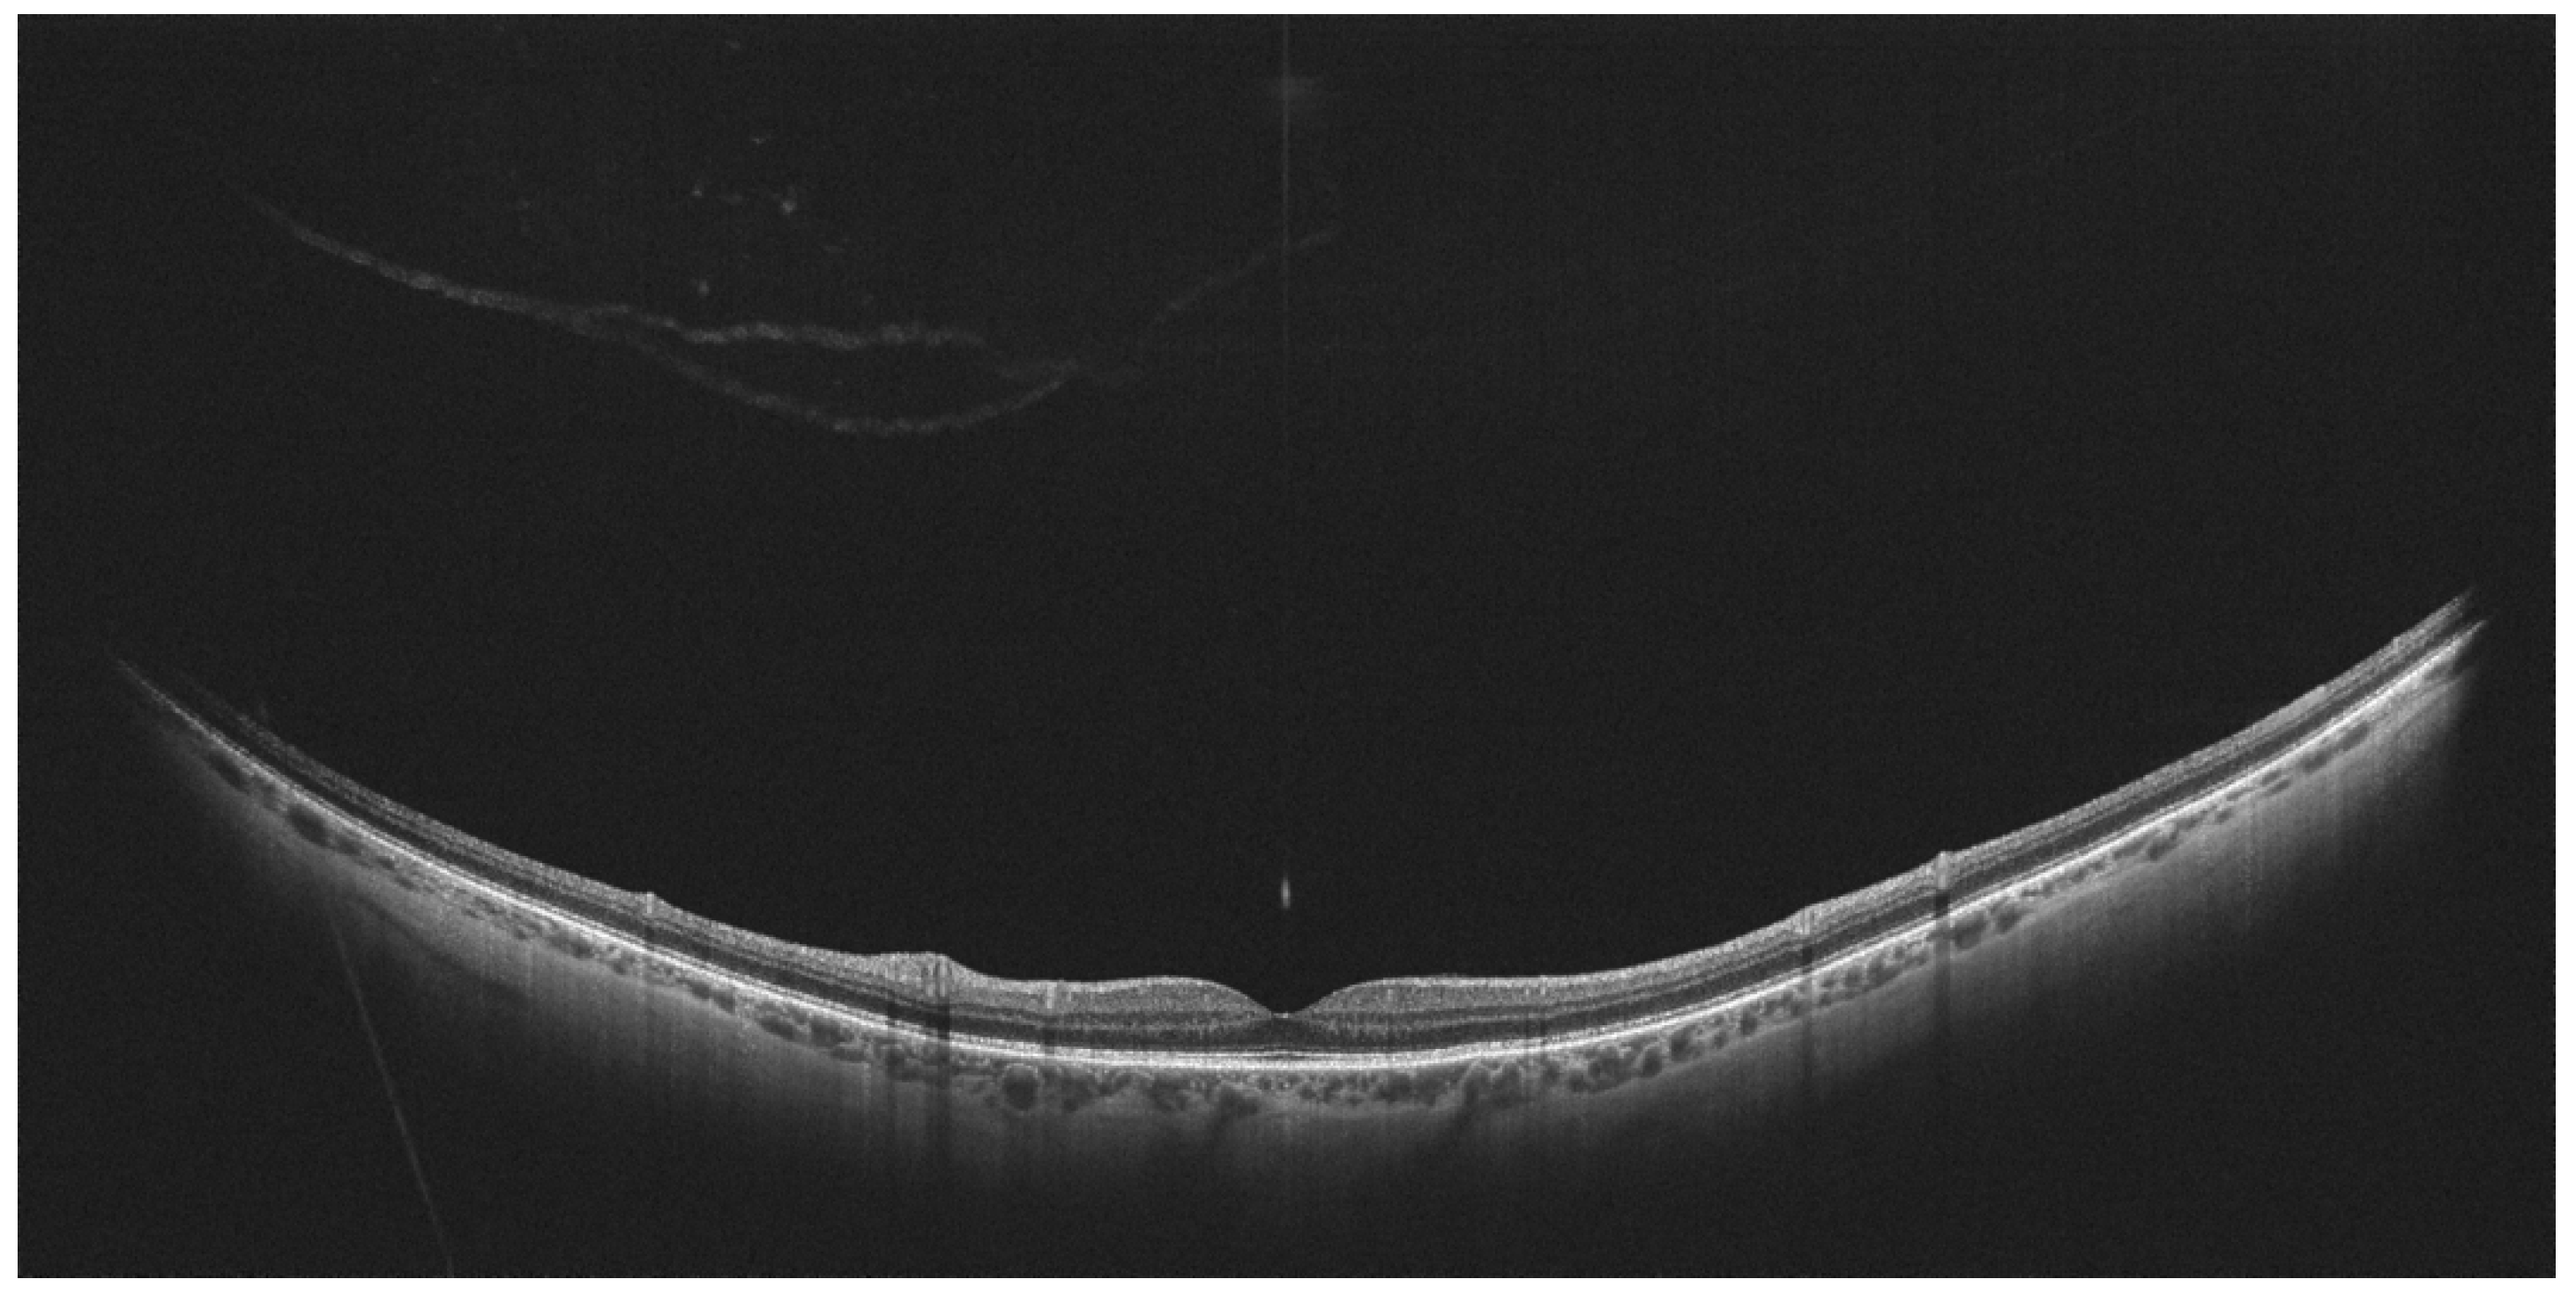

- Tsukahara, M.; Mori, K.; Gehlbach, P.L.; Mori, K. Posterior Vitreous Detachment as Observed by Wide-Angle OCT Imaging. Ophthalmology 2018, 125, 1372–1383. [Google Scholar] [CrossRef] [PubMed]